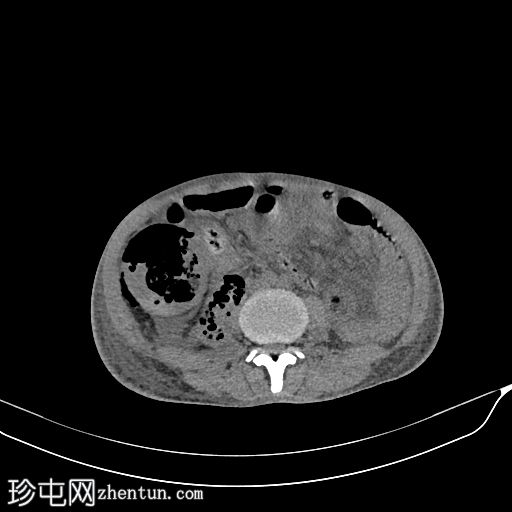

CT

轴位

平扫

双侧原肾体积较小。

移植肾位于右髂窝,增大(15 cm),肾实质被异常气体和非强化物质(坏死组织/液体)所取代,提示重度气肿性肾盂肾炎,肾实质破坏超过95%。

仅有少量肾实质强化(不足5%)。

移植肾动脉通畅。

移植肾静脉未见。

右侧腹膜后间隙及右侧腰大肌内可见中等量液体和气体,自肝下区延伸。

中度盆腔腹水。

膀胱萎陷。

弥漫性骨密度增高(?肾性骨营养不良的特征)。